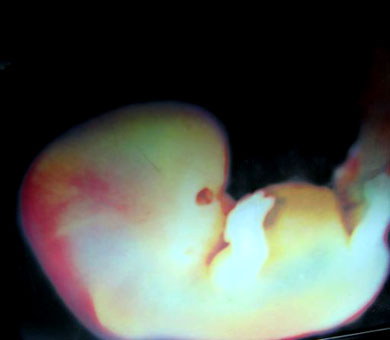

Embrion y feto.

Hasta aproximadamente decimo segunda semana de embarazo, el ovulo fertilizado se conoce como embrion.  En adelante se le llama feto.  El embrion se desarrolla muy rapido.  A las 5 semanas tiene un tamaño parecido a un grano de arroz, pero a las 12 semanas tiene aproximadamente 6 centimetros de largo.